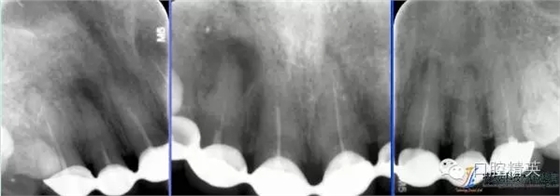

術(shù)前全景片

640.webp (4).jpg

術(shù)前根尖片

640.webp (5).jpg

術(shù)后根尖片

640.webp (6).jpg